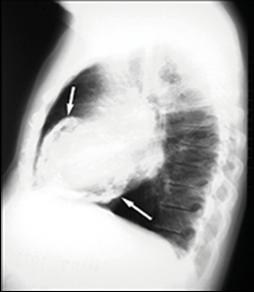

Derrame pericárdico severo da imagen en botellón en la radiografía de tórax. (ENAM EXTRA 2021)

(ENAM EXTRA 2022) (ENARM 2021)